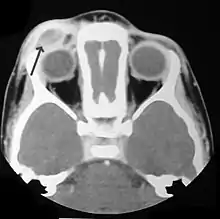

Imaging may be evident in chest X-rays with micronodular and reticular changes of the lungs with cyst formation in advanced cases. MRI and High-resolution CT may show small, cavitated nodules with thin-walled cysts. MRI scan of the brain can show three groups of lesions such as tumourous/granulomatous lesions, nontumourous/granulomatous lesions, and atrophy. Tumourous lesions are usually found in the hypothalamic-pituitary axis with space-occupying lesions with or without calcifications. In non-tumourous lesions, there is a symmetrical hyperintense T2 signal with hypointense or hyperintense T1 signal extending from grey matter into the white matter. In the basal ganglia, MRI shows a hyperintense T1 signal in the globus pallidus.[35]